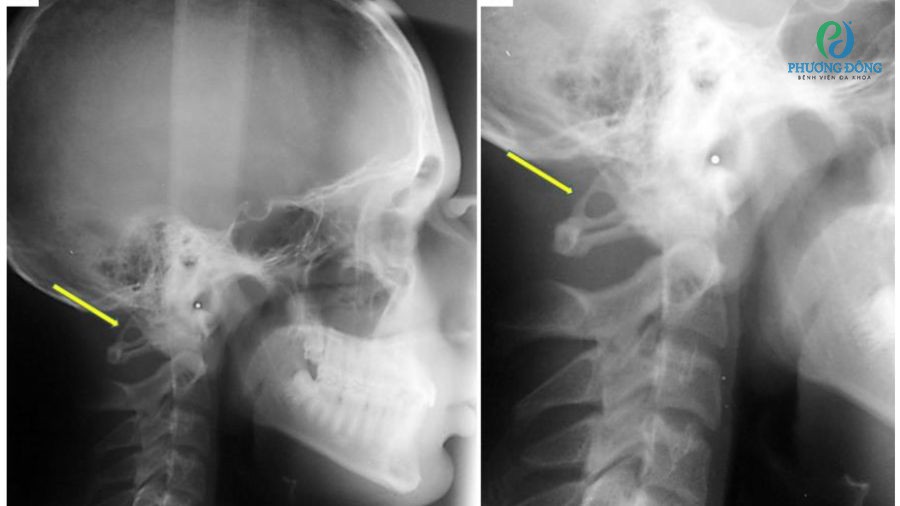

- Chụp X-quang xác định mức độ lắng đọng canxi ở dây chằng, khớp xương.

Phương pháp chẩn đoán mức độ vôi hoá tại dây chằng